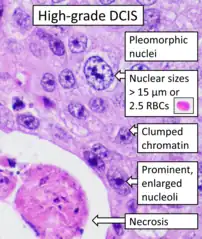

- "This article is licensed under a Creative Commons Attribution 4.0 International License" - ↑ Image by Mikael Häggström, MD. References for features:

- "Ductal Carcinoma in Situ of the Breast". Stanford Medical School. 2020-08-27.

- Hayward, M.K.; Louise Jones, J.; Hall, A.; King, L.; Ironside, A.J.; Nelson, A.C.; et al. (2020). "Derivation of a nuclear heterogeneity image index to grade DCIS". Comput Struct Biotechnol J. 18: 4063–4070. doi:10.1016/j.csbj.2020.11.040. PMC 7744935. PMID 33363702. - ↑ Image annotation by Mikael Häggström, MD, using source image from: